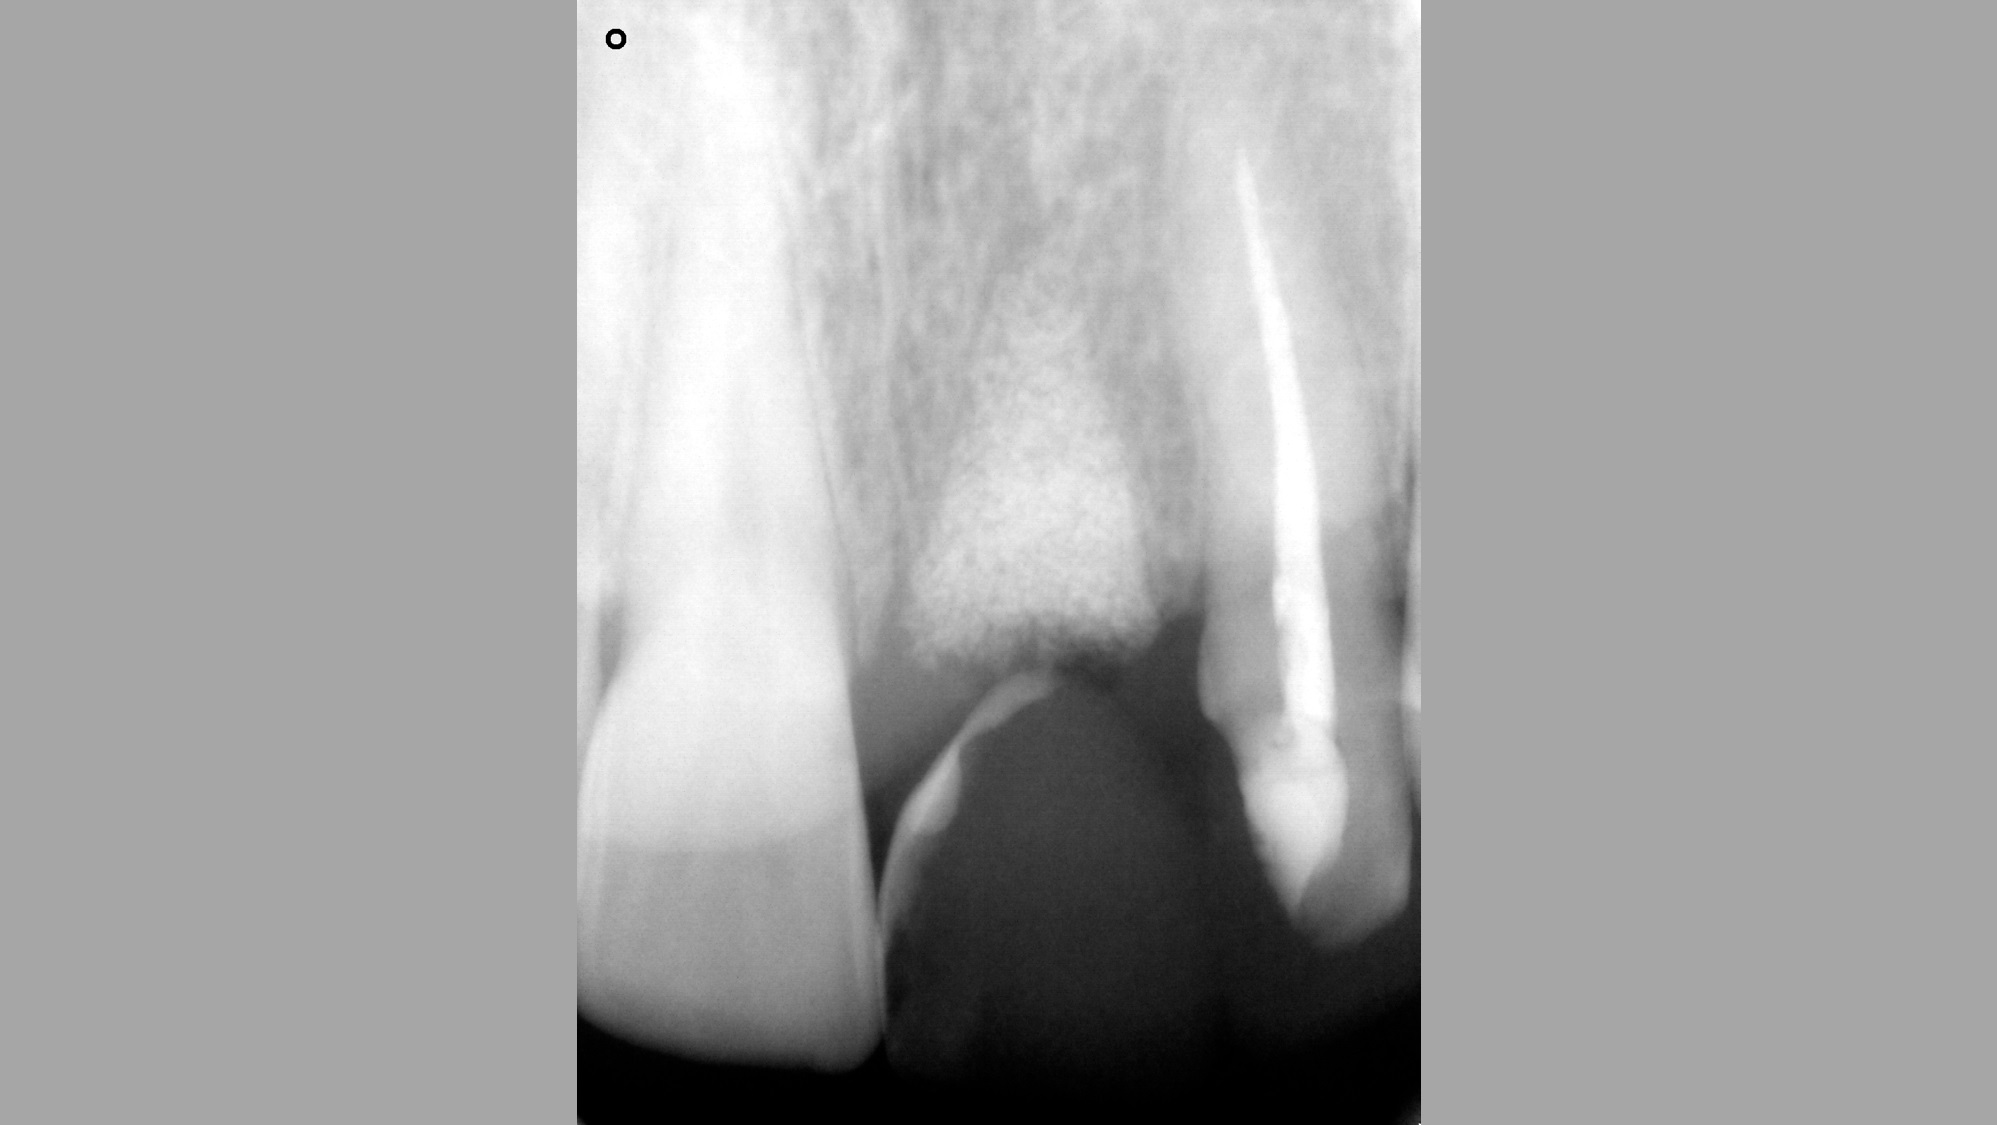

03/16 - Radiograph befor extraction of 21

Socket preservation with cerabone® - Dr. R. A. Nader